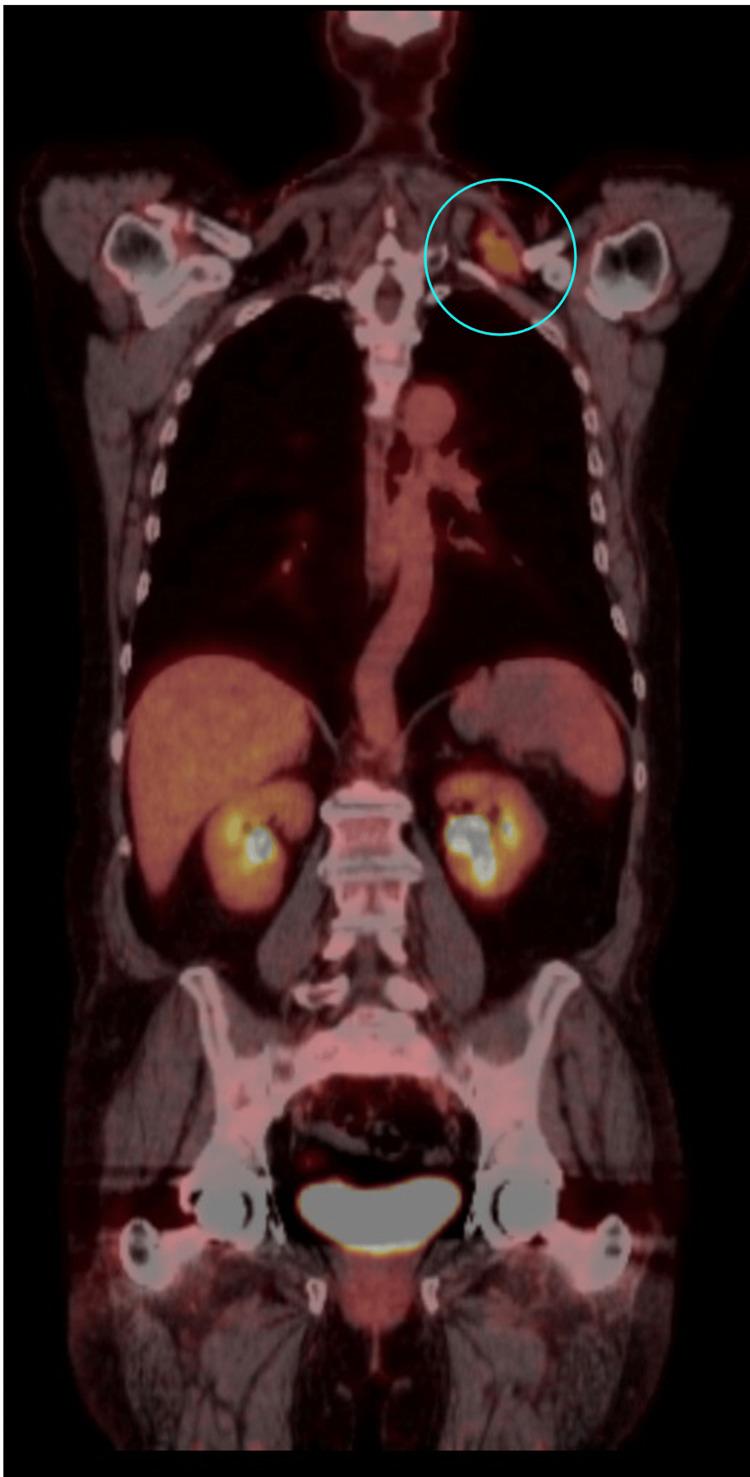

Breast cancer recurrence can occur many years after the initial treatment, particularly in hormone receptor-positive (HR+) cases, where the risk of late recurrence remains significant. Late recurrences are well documented, with research showing that they can happen even decades after the primary diagnosis, necessitating extended monitoring and personalized therapeutic approaches. A 65-year-old woman with a history of stage IIIC invasive ductal carcinoma, initially treated with neoadjuvant chemotherapy, bilateral mastectomies, adjuvant chemoradiation, and prolonged hormonal therapy, presented 10 years later with metastasis to the left supraclavicular lymph nodes. A biopsy confirmed recurrent ER+/PR+/HER2- (estrogen receptor-positive/progesterone receptor-positive/human epidermal growth factor receptor 2-negative) breast cancer. Her treatment was adjusted to include Faslodex (fulvestrant) and Verzenio (abemaciclib), followed by the surgical resection of the metastatic lymph node. Managing HR+ breast cancer involves significant challenges, mainly due to the potential for late recurrence. Even after aggressive treatment and years of remission, dormant tumor cells may become active again, leading to metastasis in less common sites, like the supraclavicular lymph nodes. This situation demands a tailored therapeutic approach, adjusting treatment strategies to address the specific characteristics of the recurrent tumor. In conclusion, late recurrence in HR+ breast cancer requires vigilant long-term follow-up and personalized treatments to effectively manage recurrence risk. Understanding dormancy and reactivation mechanisms is essential for guiding clinical decisions. Prioritizing individualized follow-up strategies and refining treatment protocols will be key to improving patient outcomes and maintaining quality of life.

乳腺癌复发可能在初始治疗多年后发生,尤其是在激素受体阳性(HR+)的病例中,晚期复发风险仍然很高。晚期复发有充分的文献记载,研究表明,它们甚至可能在初次诊断数十年后发生,因此需要延长监测时间并采取个性化治疗方法。一名65岁女性,有IIIC期浸润性导管癌病史,最初接受了新辅助化疗、双侧乳房切除术、辅助放化疗和长期激素治疗,10年后出现左锁骨上淋巴结转移。活检证实为复发性ER+/PR+/HER2-(雌激素受体阳性/孕激素受体阳性/人表皮生长因子受体2阴性)乳腺癌。她的治疗方案调整为包括芙仕得(氟维司群)和唯择(阿贝西利),随后对转移性淋巴结进行手术切除。管理HR+乳腺癌面临重大挑战,主要是因为存在晚期复发的可能性。即使经过积极治疗和多年缓解,休眠的肿瘤细胞可能会再次活跃,导致在不太常见的部位发生转移,如锁骨上淋巴结。这种情况需要量身定制的治疗方法,调整治疗策略以应对复发性肿瘤的特定特征。总之,HR+乳腺癌的晚期复发需要长期密切随访和个性化治疗,以有效管理复发风险。了解休眠和重新激活机制对于指导临床决策至关重要。优先考虑个体化随访策略并完善治疗方案将是改善患者预后和维持生活质量的关键。